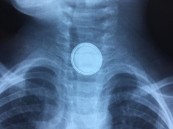

تتنبأ بالهبوط المحتمل.. مركز القلب التخصصي يراقب مرضاه عن بعد بأجهزة لاسلكية

نجح مركز القلب بمستشفى الملك فيصل التخصصي في زراعة جهاز حسّاس لاسلكي لـ 65 مريضَا بقصور عضلة القلب، لمتابعة حالتهم الصحية عن بعد.وتتنبأ التقنية بأي هبوط محتمل في وظائف عضلة القلب مسبقاً، مما يسمح بتقديم توصيات طبية فعالة لتجنبها .وتتصف ...